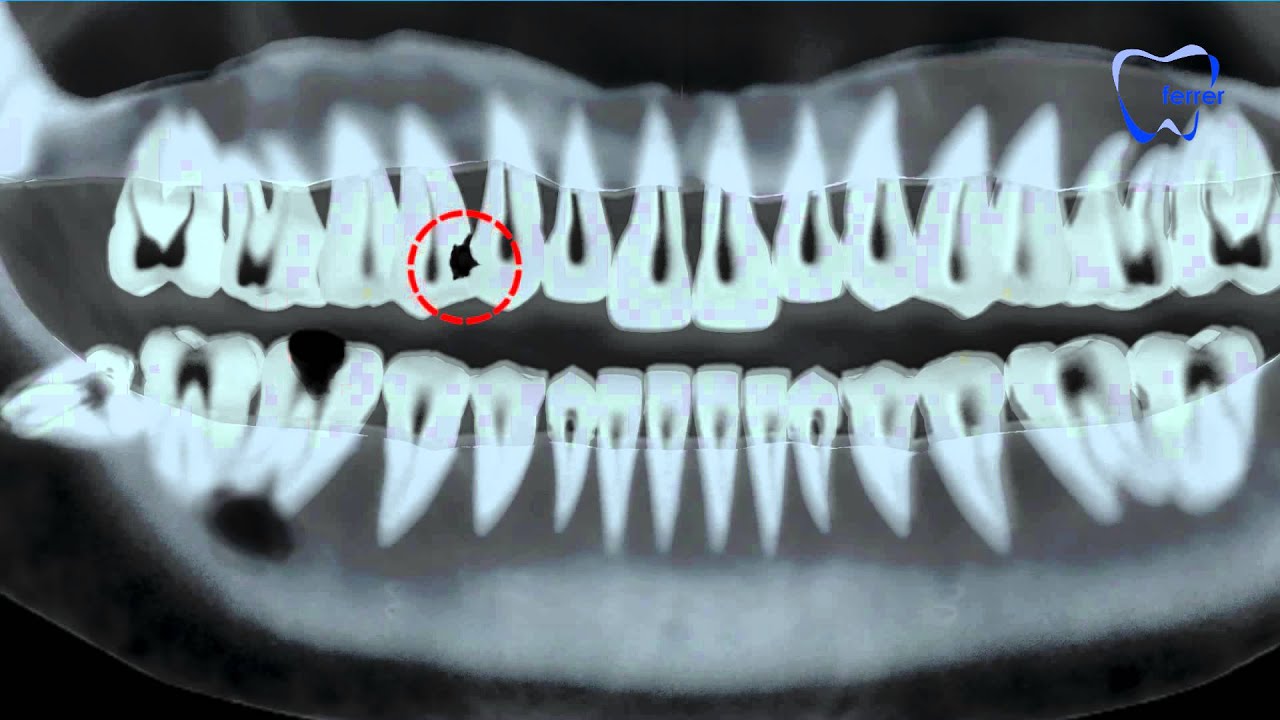

Solo con las imágenes de los dientes en rayos X de nuestra boca será posible detectar afección dental.

Cuando llevamos un tiempo sin ir al dentista y acudimos a nuestra revisión es muy recomendable realizar un control radiológico dental completo para detectar:

- La presencia de caries interproximales.

- Dientes con problemas de erupción o quistes dentales.

- Comprobar el estado de la raíz del diente y hueso para determinar el grado de avance de la periodontitis.